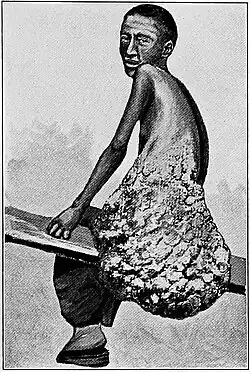

Lipomatosis is believed to be a hereditary condition in which multiple lipomas are present on the body.

Adiposis dolorosa (Dercum disease) is a rare condition involving multiple painful lipomas, swelling, and fatigue. Early studies mentioned prevalence in obese postmenopausal women. However, current literature demonstrates that Dercum disease is present in more women than men of all body types; the average age for diagnosis is 35 years.[20]

Benign symmetric lipomatosis (Madelung disease) is another condition involving lipomatosis. It nearly always appears in middle-aged males after many years of alcoholism, but nonalcoholic males and females can also be affected.[21]

Lipomas are usually relatively small with diameters of about 1–3 cm,[42] but in rare cases they can grow over several years into "giant lipomas" that are 10–20 cm across and weigh up to 4–5 kg.[43][44]